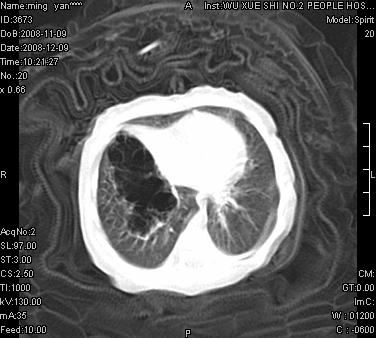

女.30天.咳嗽.喘3天.系三胞胎

考虑右肺下叶先天性肺囊肿,不除外合并右中叶肺发育不全

伴双肺感染

考虑右肺下叶先天性多发性肺囊肿可能。

考虑右肺下叶肺囊肿伴感染,右中叶节段实变或发育不全

这是一个先天性囊性腺瘤样畸形(congenital cystic adenomatid malformation,ccam),属于先天性肺发育异常,最近国外文献重新命名为先天性肺气道畸形(congenital pulmonary airway malformation,cpam),根据发生部位和畸形组织与气管、支气管的关系分成五型。本病以1岁以下婴儿多见,男性多于女性。病因为终末呼吸单元的异常增殖,形成多囊状结构。国内根据影响和病理表现分三型:ⅰ型为单个或多个大囊肿,直径大于2cm;ⅱ型为多个小囊肿,直径小于2cm;ⅲ型为大的非囊肿性病变,但显微镜下观察可见肿块由多发小囊组成(直径小于2mm)。本病可发生于肺内任何一部分,单侧肺占95%,中叶病变相对较少。